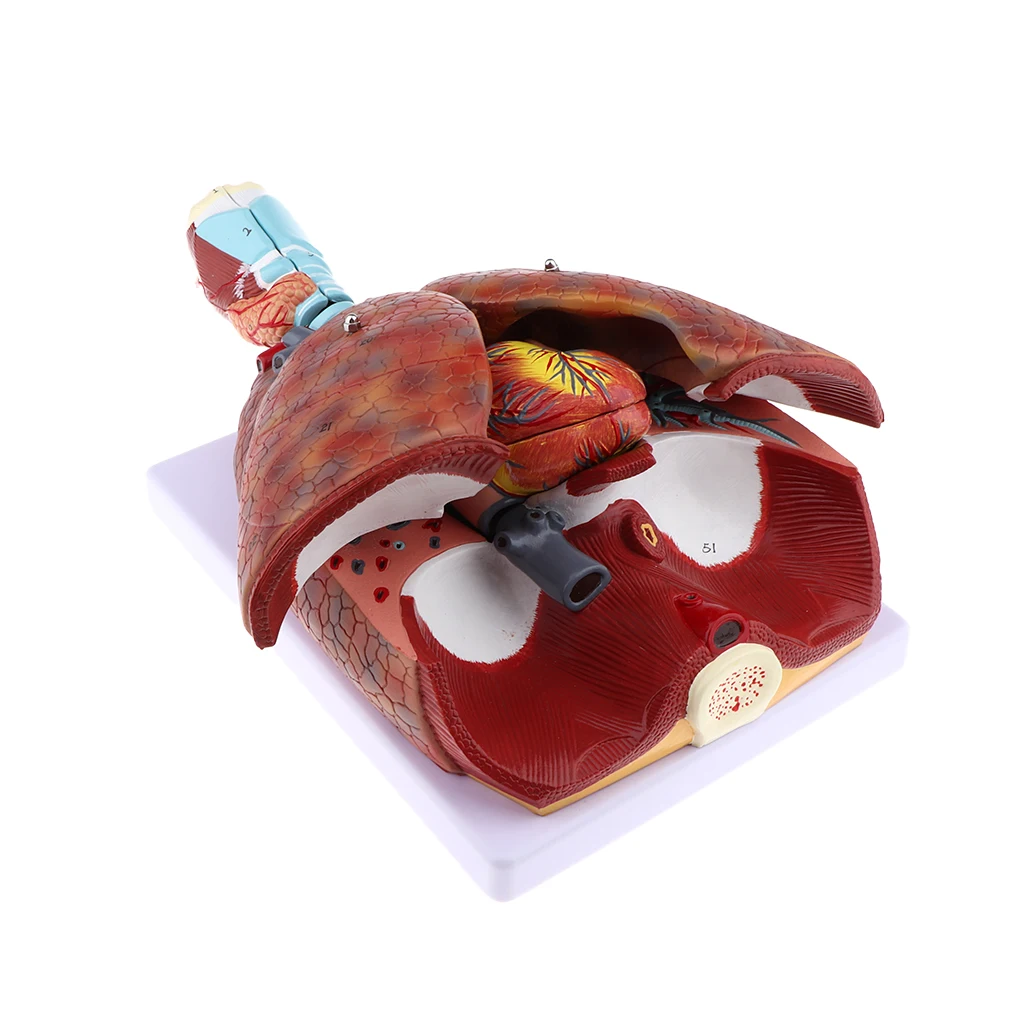

Фотографии и 3D-модели анатомии сердца человека